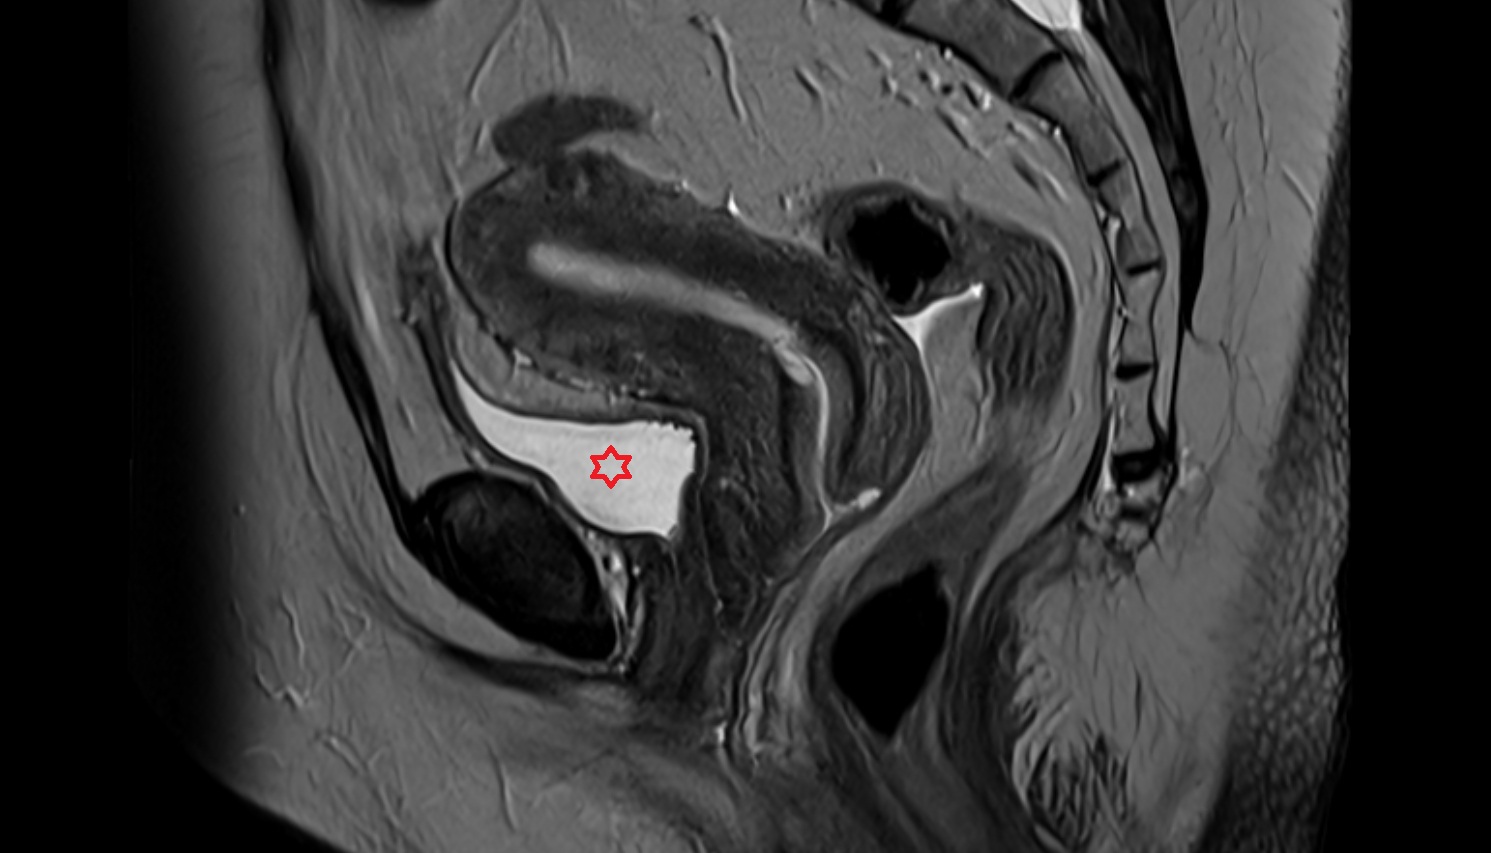

- Uterus

- Body of uterus

- Fundus of uterus

- Cervix of uterus

- Isthmus of uterus

- Vagina

- Endometrium of uterus

- Myometrium of uterus

- Junctional zone of uterus

- Urinary bladder

- Rectum